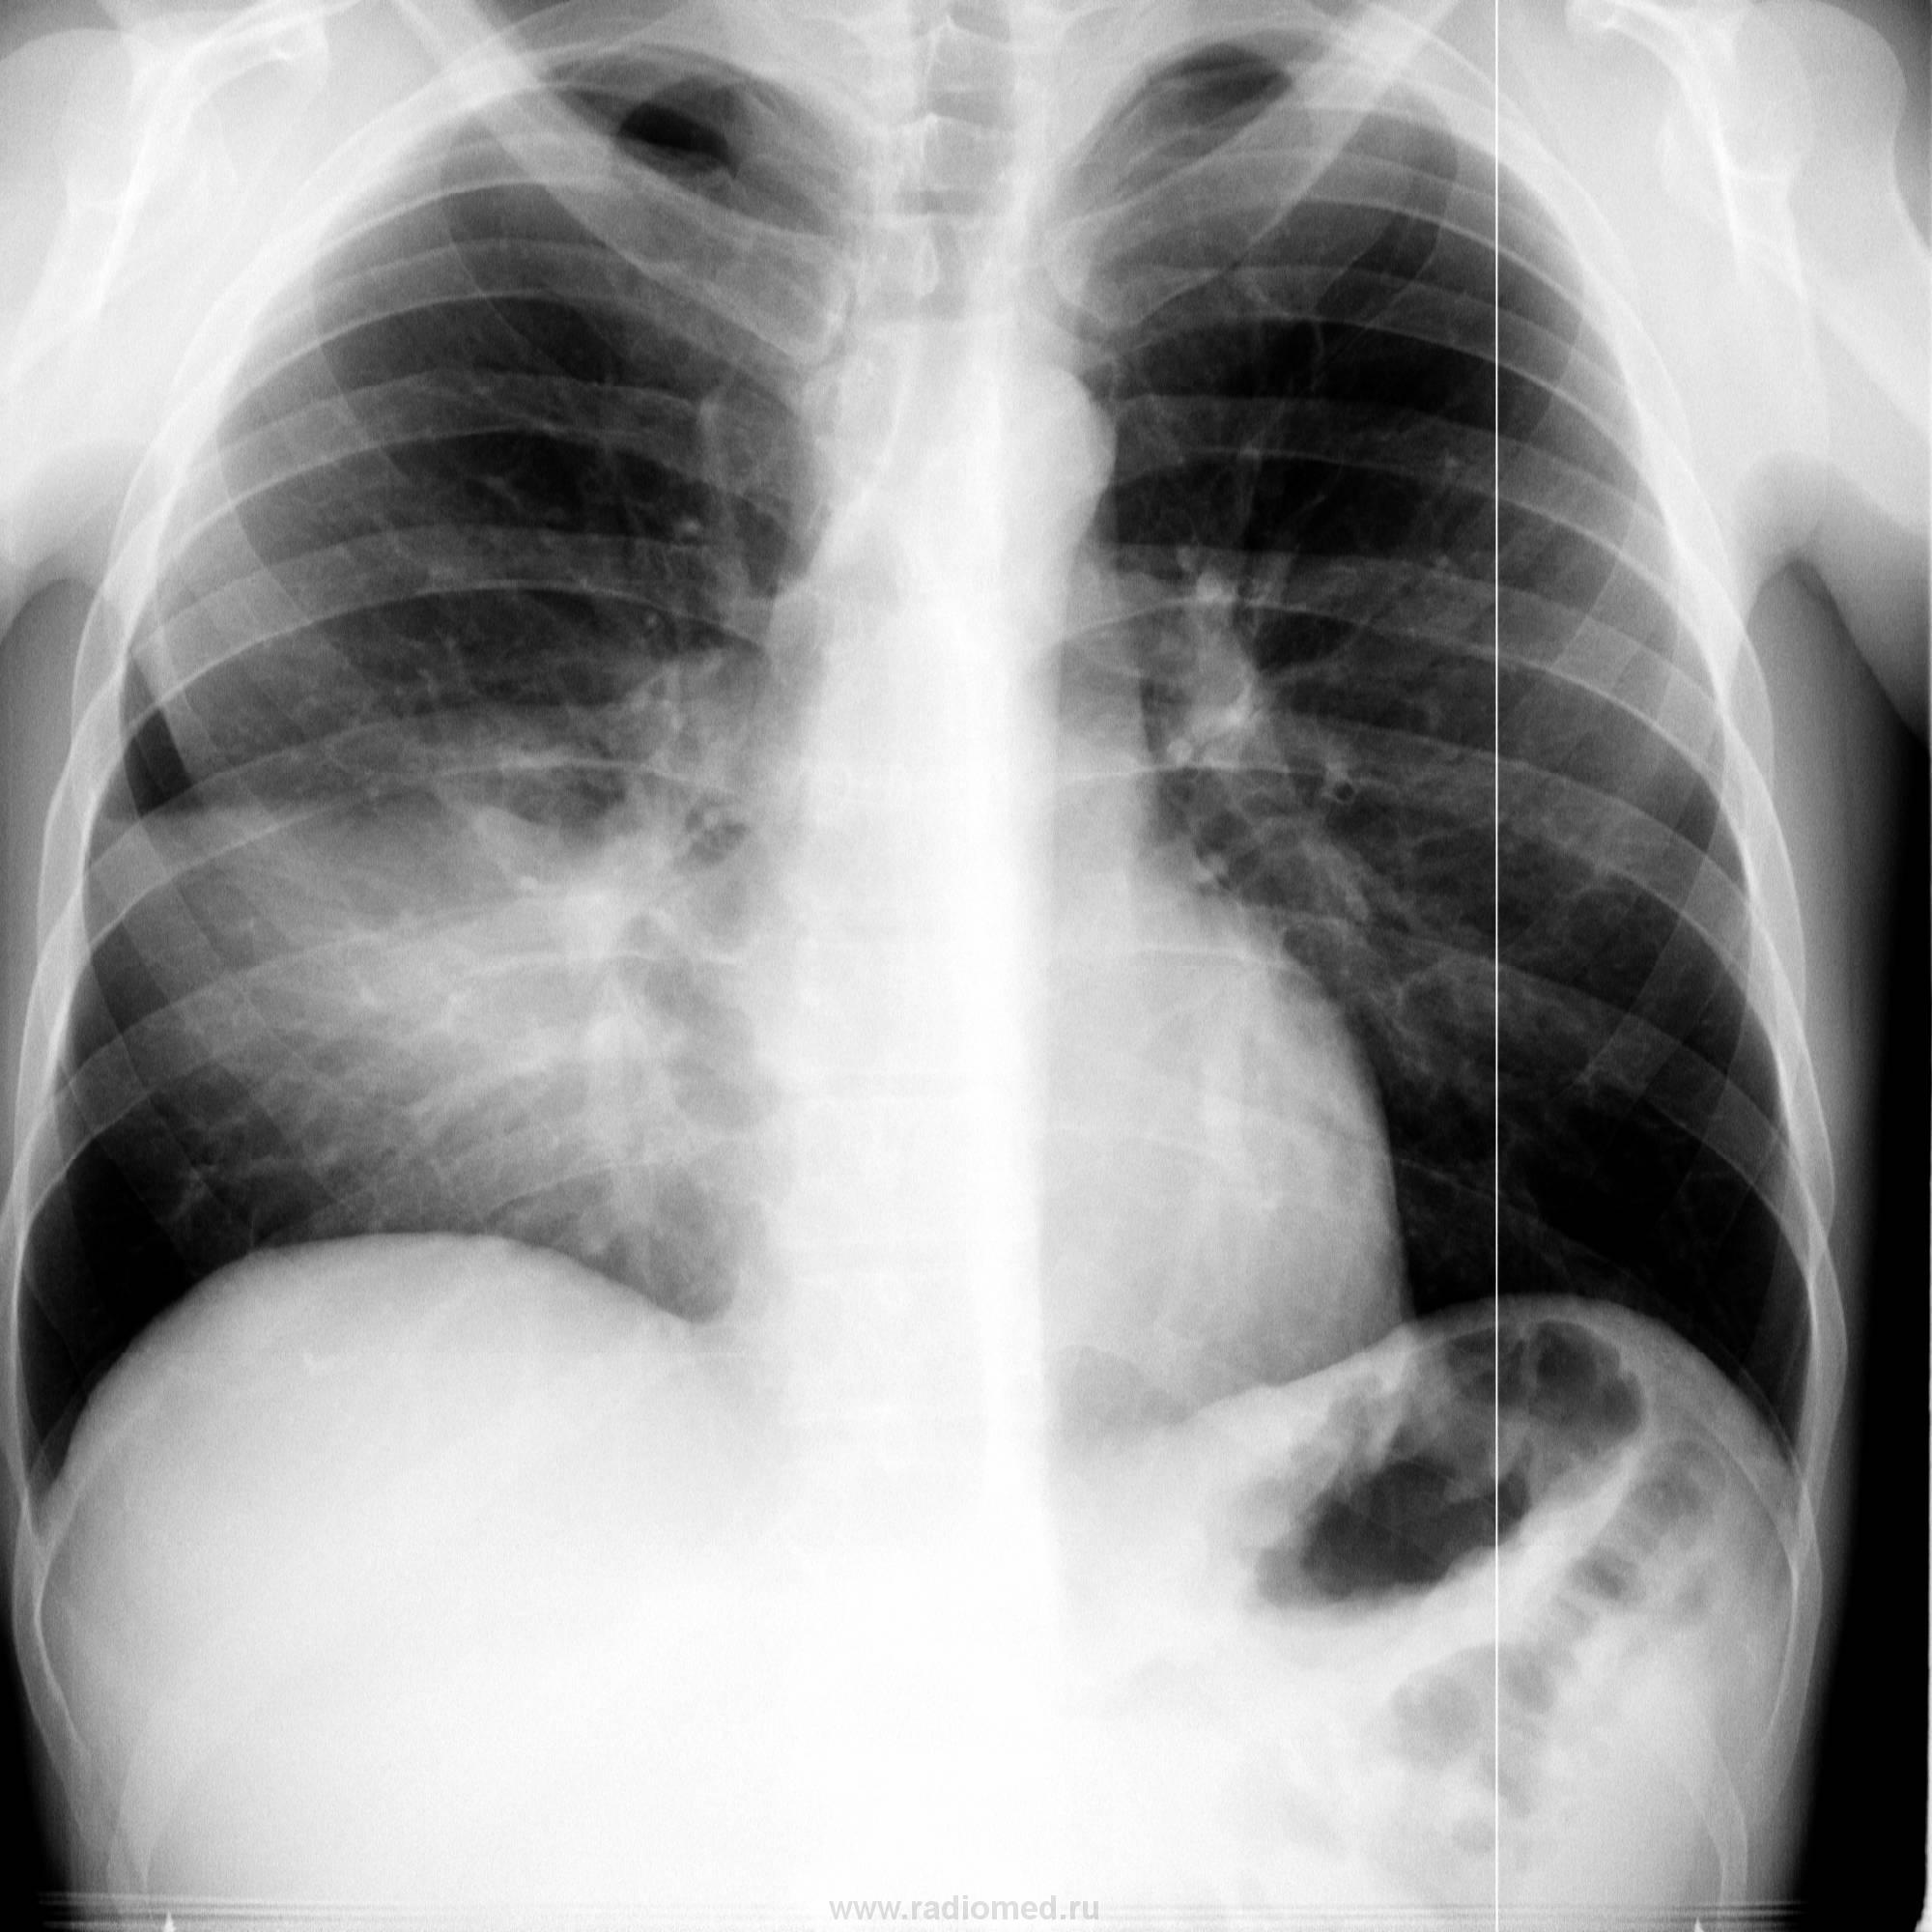

1. Классическая картина среднедолевого синдрома, в данном случае - пневмония.

2. Именно равномерное затемнение доли и просматривание легочного рисунка на этом фоне и есть особенностью, которую хотелось подчеркнуть.

Дообследование в правой боковой проекции!! Однородное затенение, на фоне которого прослеживается легочный рисунок, отграниченное междолевой плеврой. Да и клинику хотелось бы знать.

Хм, интересно во что выльется. Подпишусь. Мне, КТшнику, нечасто приходится видеть такие рентгенограммы, где в зоне такого достаточно однородного уплотнения, ограниченного долей -так прилично виден легочный рисунок.

Все, как говорится, налицо: острое начало, катаральные явления, высокая (до 38,5) температура. Госпитализирован. Если будет контроль - выставлю однозначно))))!, за мной не заржавеет)))